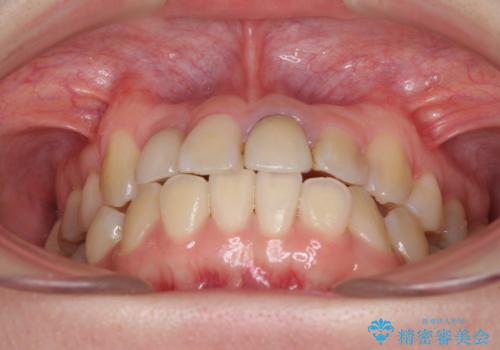

- 奥歯が痛いとのことで来院された患者様です。

上顎親知らず周辺の炎症と、神経組織の失活した歯の炎症による痛みが認められたため、親知らずの抜歯と根管治療を行いました。

根管治療を行った歯はクラウンによる補綴治療が必要となりますが、高校生の頃に行った矯正治療の後戻りも気になるとのことで、補綴治療を行う前に矯正治療を行うこととしました。

後戻りは軽度であり、インビザラインにて歯列を整え、その後にオールセラミッククラウンにて補綴治療を行うこととしました。